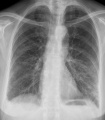

- Mohou způsobovat onemocnění, u člověka např. angínu, zápal plic, salmonelózu či lymskou boreliózu. Léky zvané antibiotika bakterie ničí či omezují jejich množení. U bakterií se však vyvíjí odolnost vůči těmto lékům (rezistence). Proti některým bakteriálním onemocněním (např. černému kašli, záškrtu) existuje očkování.